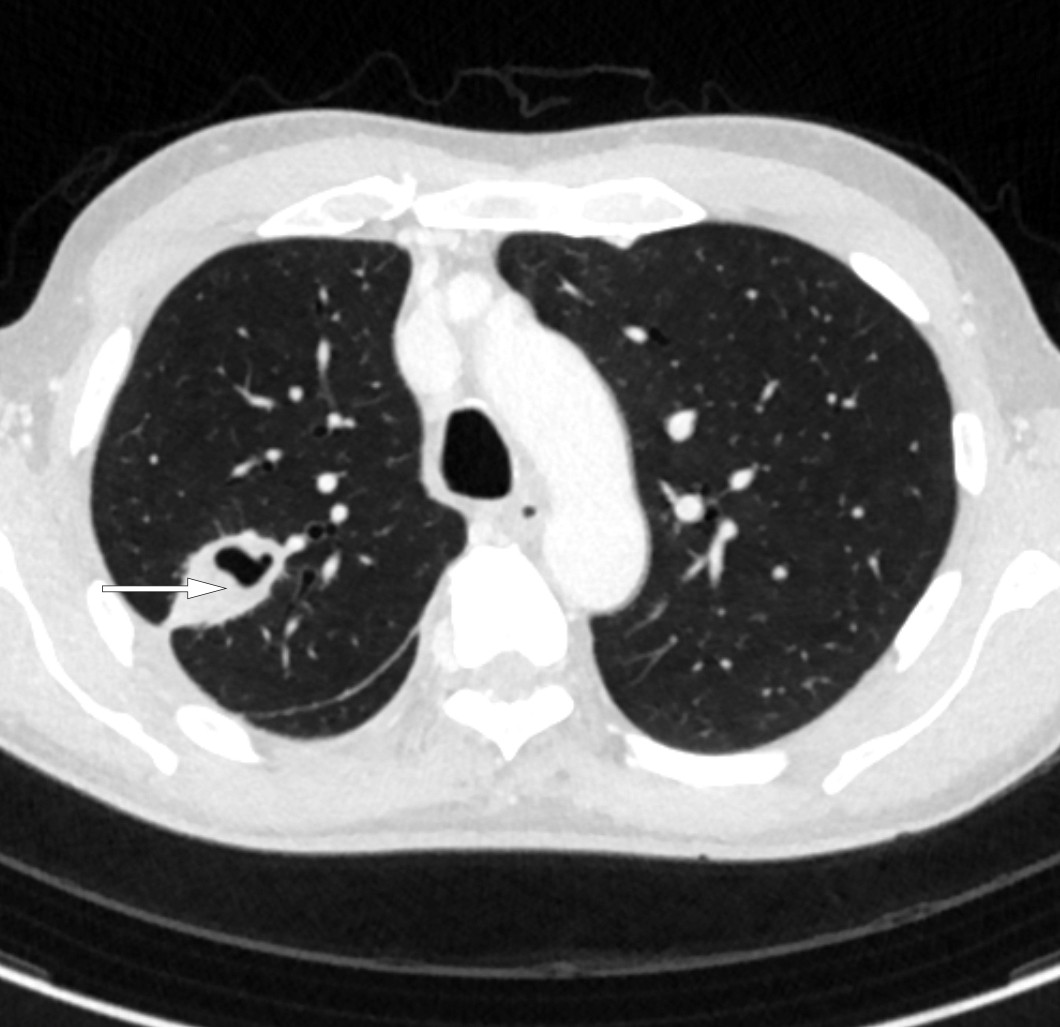

CT thorax (figur 3) to dager etter innleggelse viste basalt i høyre lunges overlapp en konsolidert fortetning med sentral luft, en kaverne, med største diameter 58 mm. Ved siden av denne var det tre-i-knopp-forandringer og flere mikronoduli. Pleurahinnen rundt pleuravæsken var fortykket med økt kontrastoppladning med inntilliggende fortetninger både i underlapp og midtlapp. Noen lymfeknuter i høyre hilus og mediastinum var forkalket og større enn normalt. Apikalt medialt i venstre lunges overlapp var det en mindre irregulær fortetning på rundt 1 cm med omkringliggende små mikronoduli, men ingen pleuravæske. Det ble stilt spørsmål om fortykket perikard.

Tre-i-knopp er en betegnelse på en subtype av sentrilobulære fortetninger som indikerer bronkiolitt, ofte assosiert med aktiv infeksjon (2).